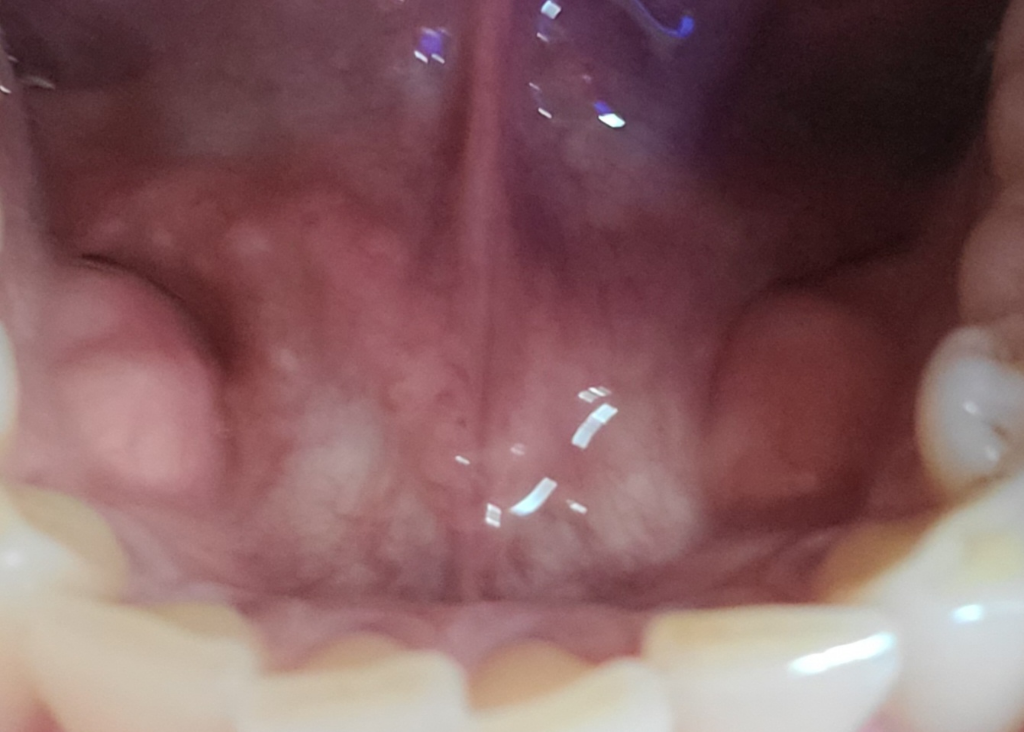

아래 치아 안쪽에 돌기 같은것이 생겼는데 무엇 인지요?

사진 아래치아 안쪽에 돌기 생김 걱정됩니다.혹시 무엇 인지요?

딱딱한데 아프지는 않습니다.

사진의 소견을 통해 보았을 때에는 특별히 이상 소견으로 보이지는 않습니다. 딱히 병적인 상태로 보이지 않으며 치료가 필요해 보이지는 않지만 걱정되신다면 치과병원에서 검진을 한 번 받아보시길 권고드립니다.